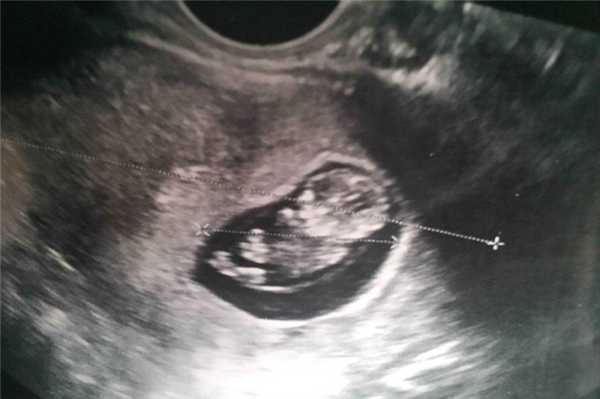

Фото УЗИ ребенка на 11 неделе беременности

На этом сроке малыш увеличивается до 45-60 мм, что позволяет отчетливо видеть его на снимке УЗИ. Его сердцебиение лежит в пределах 120-160 ударов в минуту. Происходит формирование дыхательной системы.

На фото видны такие изменения плода:

- руки малыша, длиннее ног, а размеры головы сопоставимы по размерам со всем остальным телом;

- у плода формируется шея, что позволяет ему совершать движения головой;

- между пальцами пропадают перепонки, ребенок пытается сжимать их в кулачки и разжимать;

- в связи с полным отсутствием жировой ткани, на УЗИ видны сосуды, просвечивающиеся через кожу;

- шевеления плода еще слабые, но они видны на экране прибора;

- начинается формирование гениталий.